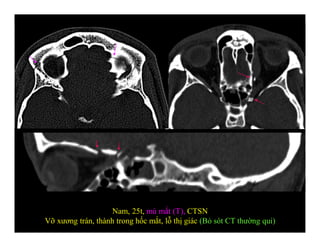

Nam, 25t, mù mắt (T), CTSN

Vỡ xương trán, thành trong hốc mắt, lỗ thị giác (Bỏ sót CT thường qui)

Nam, 25t, mùmắt (T), CTSN Vỡ xương trán, thành trong hốc mắt, lỗ thị giác (Bỏ sót CT thường qui)